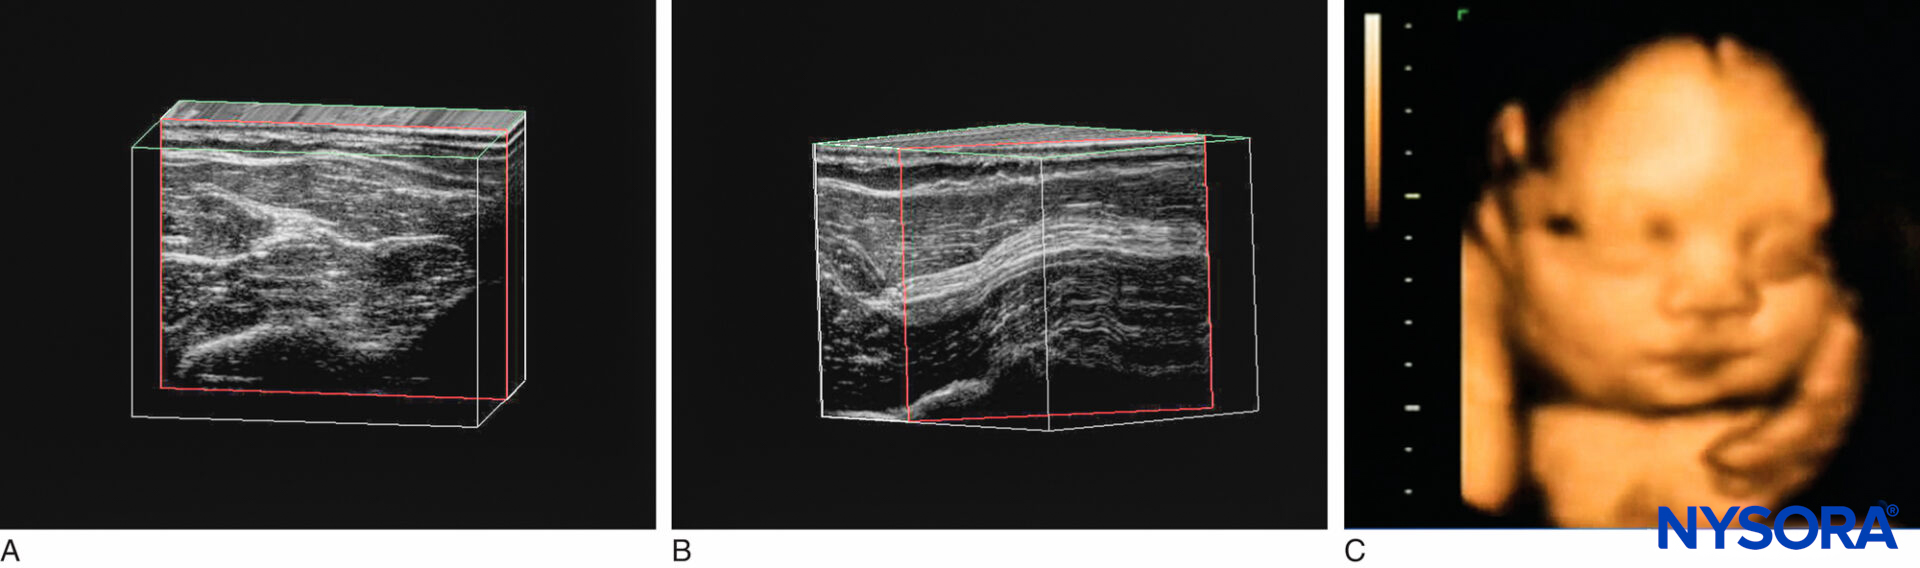

The ultrasound machines currently used in regional anesthesia provide a 2D image, or “slice.” Machines capable of producing three-dimensional (3D) images have recently been developed. Theoretically, 3D imaging should help in understanding the relationship of anatomic structures and the spread of local anesthetics. There are three major types of 3D ultrasound imaging: (1) Freehand 3D is based on a set of 2D cross-sectional ultrasound images acquired from a sonographer sweeping the transducer over a region of interest (Figures 18A and 18B). (2) Volume 3D provides 3D volumetric images using a dedicated 3D transducer. The transducer elements automatically sweep through the region of interest during the scanning; the sonographer is not required to perform hand motions (Figure 18C). (3) Real-time 3D takes multiple images at different angles, allowing the sonographer to see the 3D model moving in real time. However, typical spatial resolution of 3D imaging is about 0.34–0.5 mm. At present, 3D imaging systems still lack the resolution and simplicity of 2D images, so their practical use in regional anesthesia is limited.

Figure 18. A: Freehand 3D imaging. A linear transducer produces parallel scan lines and a rectangular display; linear scan. B: Freehand 3D imaging. A curved “phase array” transducer results in a curvilinear scan and an arch-shaped image. C: Fetal face viewed by volume 3D imaging. (Reproduced with permission from Hadzic A: Hadzic’s Peripheral Nerve Blocks and Anatomy for Ultrasound-Guided Regional Anesthesia, 2nd ed. New York: McGraw-Hill, Inc; 2011.)